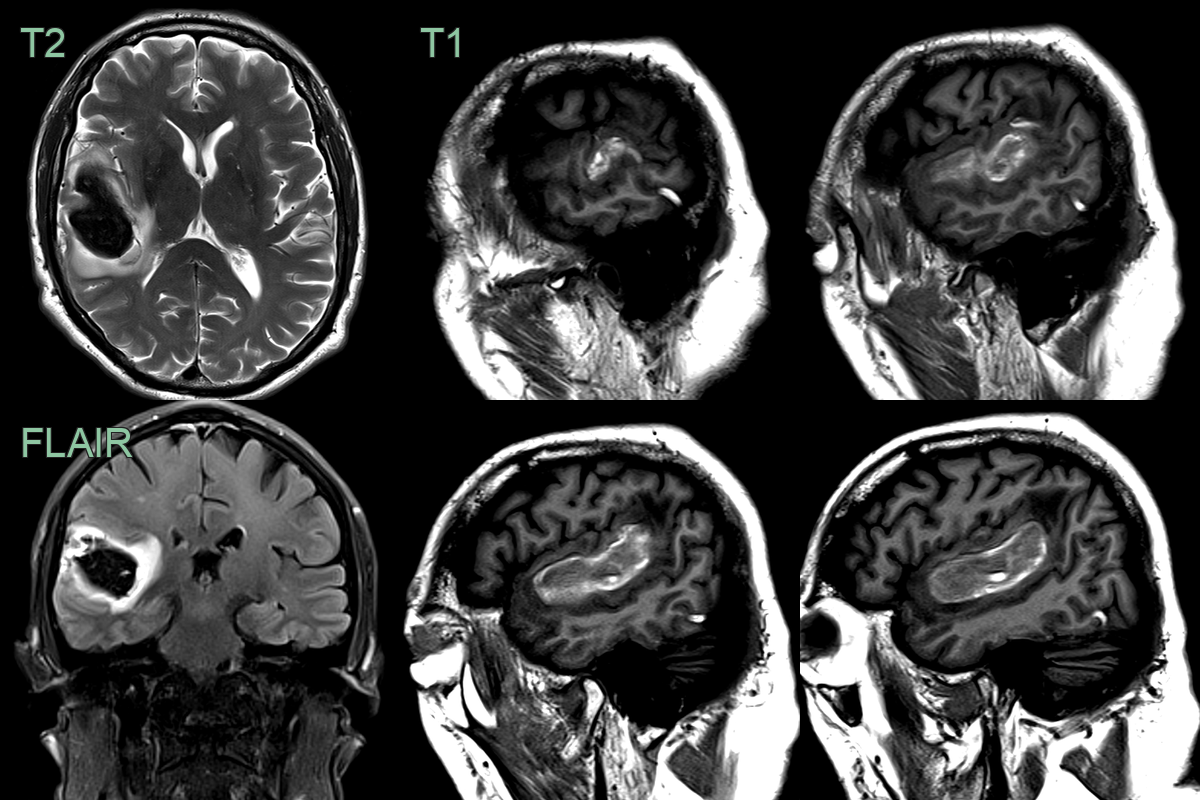

• A 60-year-old patient presented with a headache following a gastrointestinal illness.

• MRI showed a large hematoma centred on Heschl's gyrus.

• Serpigionous T1-hyperintensity over the temporal lobe represented acute thrombus in the vein of Labbe.